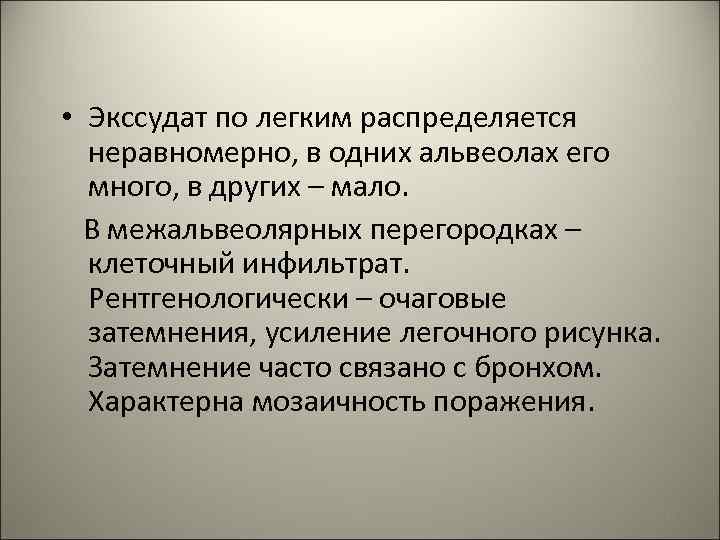

• Патанатомия. Очаги воспаления при бронхопневмонии обычно возникают в задних и задненижних сегментах легких, при этом развивается: I. Серозное воспаление вокруг бронхов (бронхит). II. В альвеолах экссудат с примесью слизи, много нейтрофилов, макрофагов, эритроцитов, небольшое количество фибрина. 66

• Экссудат по легким распределяется неравномерно, в одних альвеолах его много, в других – мало. В межальвеолярных перегородках – клеточный инфильтрат. Рентгенологически – очаговые затемнения, усиление легочного рисунка. Затемнение часто связано с бронхом. Характерна мозаичность поражения. 67